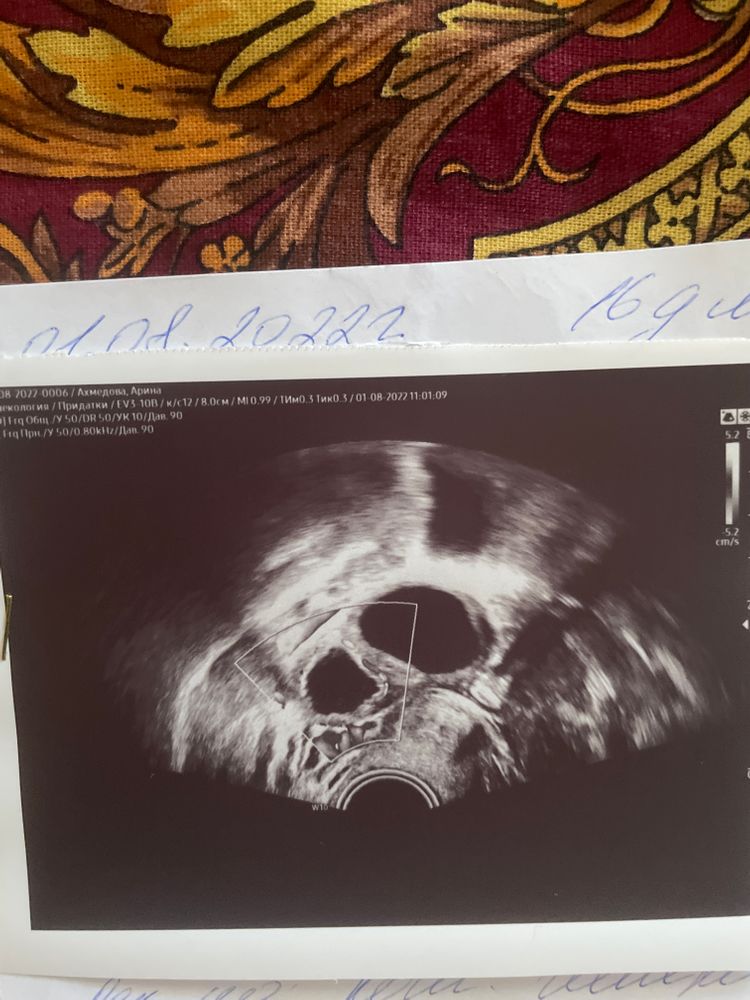

16д.ц. на узи не определили была ли овуляция и желтое тело это или нет.

Похоже на ЖТ тк в желтом теле формируются перегородки

Арина, да уж, заключение фолликулометрия 😅специалист конечно так себе был у вас. скорее всего овуляция произошла исходя из того что вы прислали, жидкость + перегородка- признаки овуляции

Арина, в ещё эндометрий должен быть светлее матки, это означает что начались изменения под действием прогестерона. Так же можете сдать на прогестерон анализ крови если хотя бы 5-6-7 то овуляция точно была и это желтое тело

Похож на ЖТ тот, что меньшего размера. И рядом фолликул ещё похоже) а эндометрий какой?

Tania, эндометрий 9,7

Вроде похоже на жт, а рядом еще ДФ